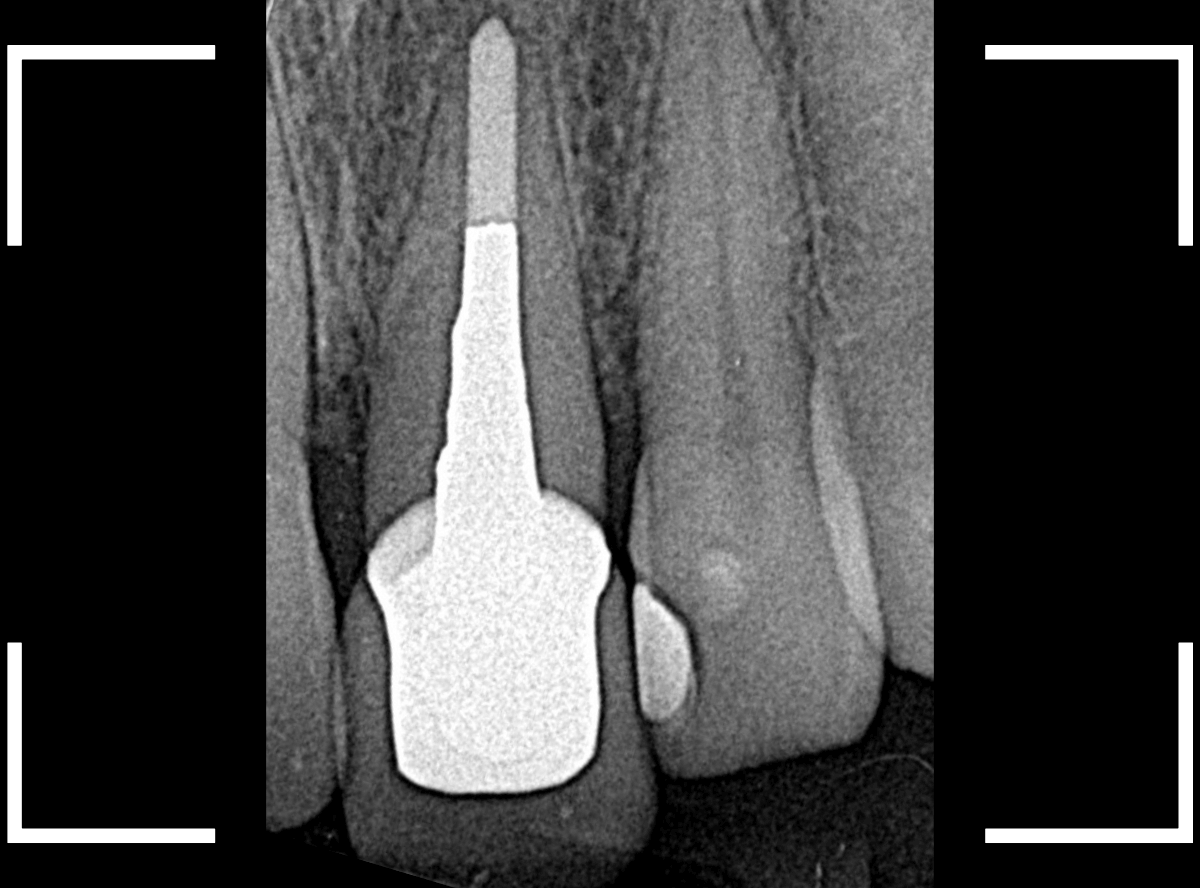

検査をすると、さし歯の周りの歯肉から出血が多いため、レントゲン写真で確認すると、さし歯の中で虫歯が進行していると診断されました。

神経を取っているさし歯の中の虫歯は、レントゲン写真でも正確にはわからず痛みもないため、さし歯をはずしてみないと、どれくらい進行しているかははっきりわかりません。 虫歯と診断されたさし歯の中は一体どうなっているのでしょうか?

さし歯の中には大きなメタル・コアが入っています。。。

さし歯の周りの歯肉が若干黒ずんでるのも、これが原因でしょう。

せっかくさし歯をやり直すのであれば、このメタル・コアもやりなおしたいところです。

かなり怖かったですが、患者さんにも頑張っていただいて、さし歯を除去後、時間をかけて慎重にメタルコアを除去しました。

無事にメタルコアを除去できましたので、ファイバーコアに置き換えます。